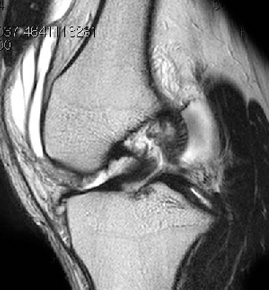

ACL 손상 방사선 사진1